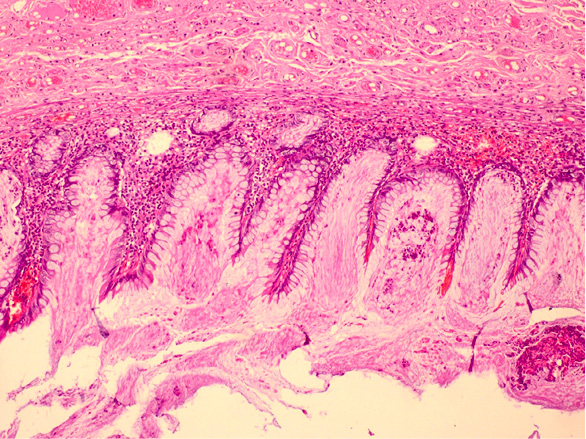

Figure 2. Villiform mucinous epithelial proliferation appears to replace the normal appendix mucosa

Pathologically, the appendix lumen diameter was 1.7 cm in the widest area. The appendix’s long axis was 7.5 cm. Mucoid material was observed in the lumen. The pathologic diagnosis was low-grade appendiceal mucinous neoplasm (appendiceal villous adenoma). Villiform mucinous epithelial proliferation was observed to replace the normal appendix mucosa [Figure 2]. It was observed that lymphoid tissue decreased In lamina propria and was replaced with fibrotic connective tissue [Figure 3]. Villiform mucinous epithelial proliferation appears to be composed of long mucinous epithelial cells with a low degree of nuclear atypia [Figure 4].